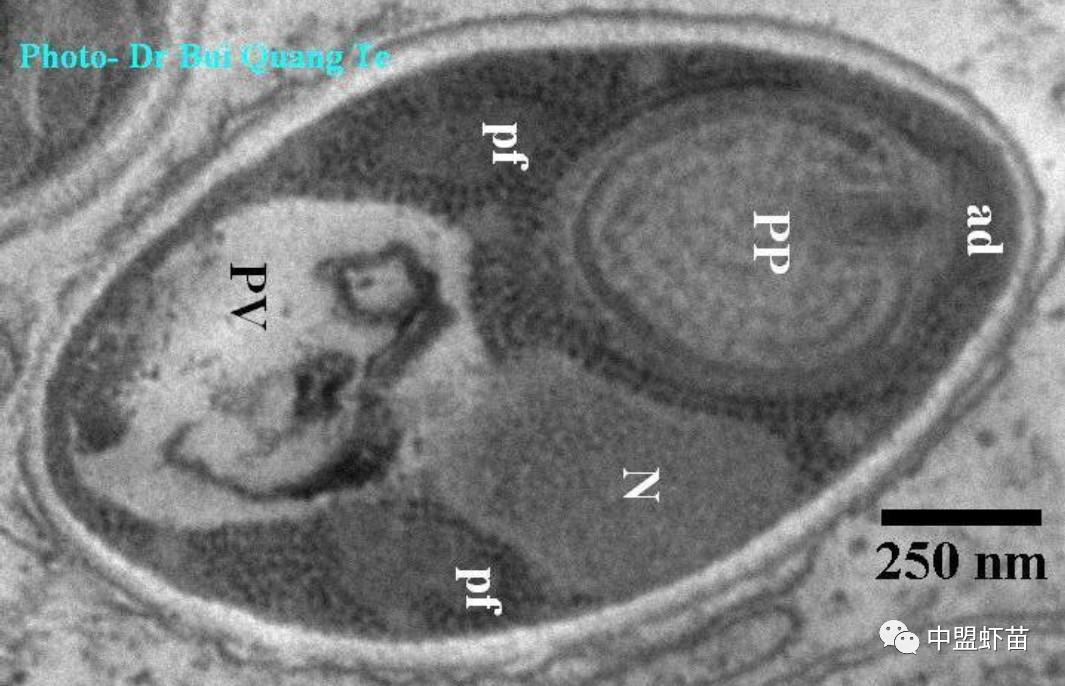

成人孢子电子显微镜垂直切成椭圆形,尺寸为0.60 x 1.86μm,前面有囊性极(PP),前端为粘附盘(ad),后面有液泡(PV),中间有1个核(N),上两侧有细丝 (pf)(图10-11)。 孢子阶段在宿主细胞质(肝胰腺细胞)中发育,宿主细胞表面含有许多小颗粒(泡)。

图11:孢子切椭圆形,正面有有囊性极(PP),前端有附着盘(ad),后面有液泡(PV),中间有1个核(N),两侧杆有细丝 (pf)。